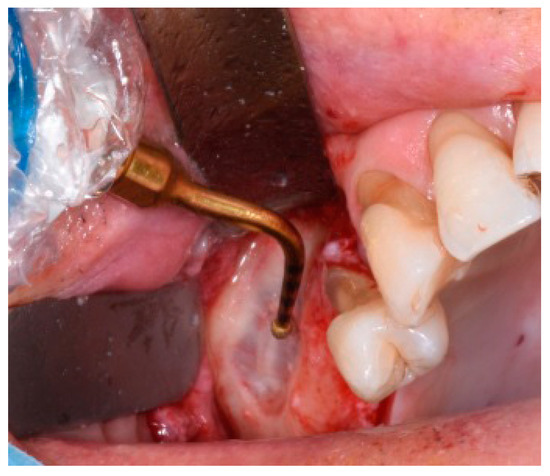

2.2. Sinus Floor Lift Surgery